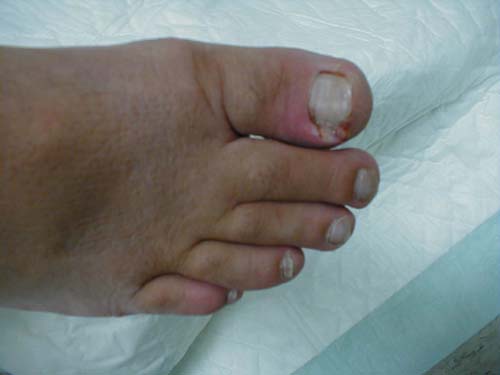

الفطار الظفري

خمج فطري مزمن أدى إلى إحداث تغير في لون الأظافر مع تشوهها .